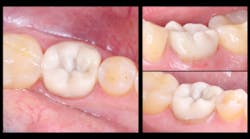

This is a case report of a tooth that was previously restored using a direct technique and a glass ionomer restoration. When the restoration failed, it completely debonded from the tooth surface, and minimal tooth structure remained (figures 1 and 2). When treatment options were discussed with the patient, he refused all traditional restorative therapies. In fact, he refused any preparation of his remaining tooth structure and requested that the tooth be restored with a direct glass ionomer restoration.

Figure 1: Lateral view at initial presentation

Figure 2: Occlusal view at initial presentation